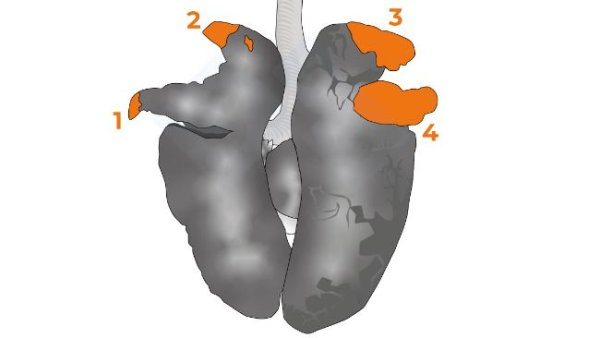

In this second installment, we cover extracting the tongue, trachea, lungs, and heart in one piece. We will extract the organs of the abdominal cavity, both the digestive system and the urinary and genital tracts. In the head, we will access the nasal turbinates, brain, and cerebellum.

In the fourth installment of the manual, we address examining the thoracic cavity organs.